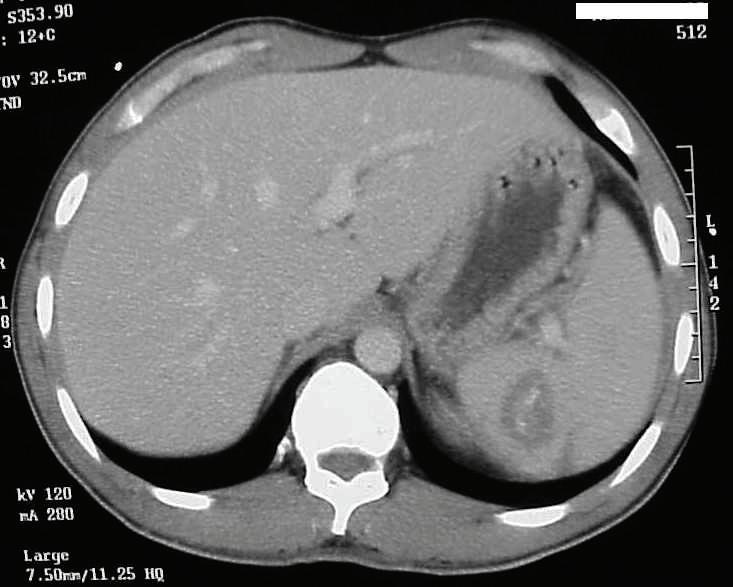

20-годишна бременна жена в 29 ге -

стационна седмица, примигравида, е хоспитализирана в Клиниката

по акушерство и гинекология на УМ -

БАЛ ,,Д-р Георги Странски” – гр. Пле -

вен с преждевременно пукнат око -

лоплоден мехур, високи стойности на артериалното налягане (150/100 mmHg) и изразени отоци по долните крайници. Пациентката е с придружаващо заболяване ЗДТ1, диагностициран в детска възраст, на терапия с бързодействащ инсулинов аналог (Glulisine) и дългодействащ инсули -

нов аналог (Glargine). Анамнестичните данни показват, че пациентката е с

повишено артериално налягане от 20 дни със стойности до 160/100 mmHg,

кифосколиоза, силно раздути дебелочревни бримки, ехопозитивни тънкочревни бримки, единична пъпна артерия, десностранно криво ходило, съмнение за артрогрипоза на големите стави, отговарящи на caudal regression sequence.

Физикалният преглед на бременната показа нормална белодробна функция с везикуларно дишане без добавени хрипова находка и норморитмична, нормофреквентна сърдечна дейност с АН 150/100 mmHg.

околоплодна течност, което затруднява визуализацията на вътрешните органи на плода. Прави впечатление

на същите. Проведе се токолитична терапия, антибиотична

провежданата антихипертензивна терапия.

На третия ден от хоспитализацията мултидисциплинарен екип обсъди по-нататъшното поведение. Взе се решение за родоразрешение чрез Цезарово сечение в интерес на майката поради екстремно незрелия гестационен срок, седалищно пред

персистиращите високи стойности на артериалното налягане и

от УЗИ за малформативен плод.